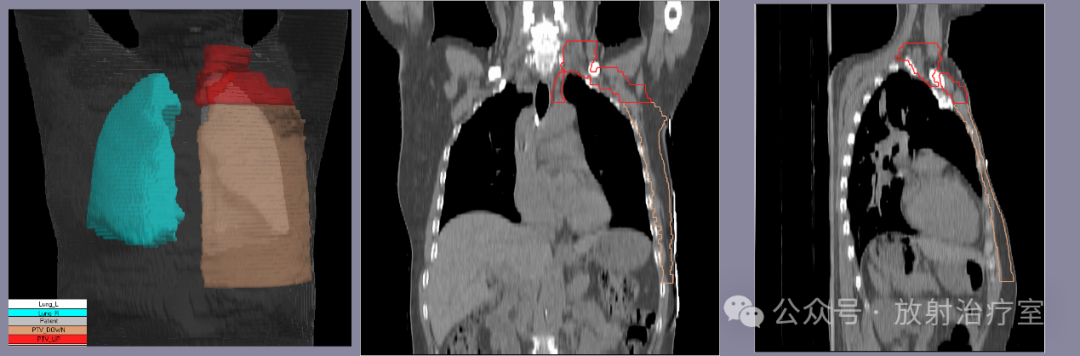

图片